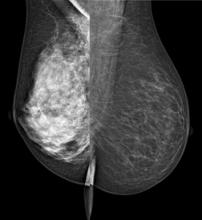

Positron emission mammography (PEM) is an imaging technique designed to provide metabolic visualization of lesions in the breast tissue. The Naviscan high-resolution PEM system is a dual-detector system consisting of two flat, high-resolution detector heads using lutetium yttrium oxyorthosilicate in a 2 x 2 x 13 mm size. The detectors are mounted inside mammogram compression paddles with a 17 x 24 cm field of view.  The paddles can be rotated to optimize imaging to match images acquired in standard mammograms.  This allows for direct comparison with mammogram images.